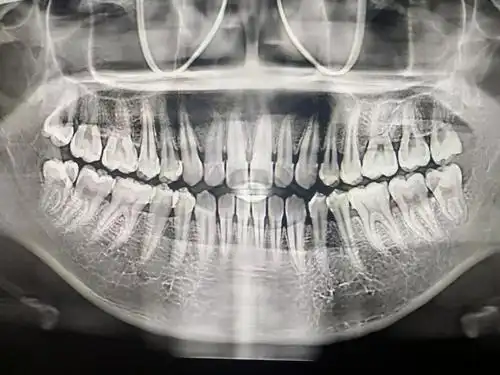

9张图教你如何看牙片#医学科普 - 抖音

每个人都有必要去牙科拍牙片检查一下,说不定就有小惊喜

牙片中你的牙都可爱吗?